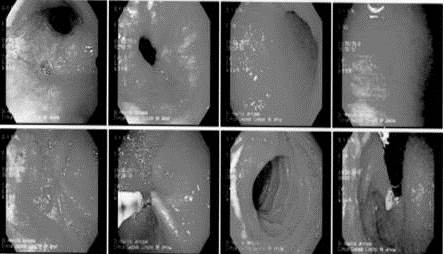

El 30 de enero de 2018, se le realizó una endoscopia digestiva alta por indicación de dispepsia persistente, en la que se observaron anomalías en la mucosa esofágica con aspecto eritematoso en la parte distal del esófago (esofagitis distal grado A), no se visualizaron úlceras. La mucosa gástrica se localizó eritematosa en toda la extensión, con presencia de erosiones elevadas en el antro y cuerpo de los cuales se tomó muestra para prueba de ureasa y estudios histológicos, el diagnóstico de relevancia fue pangastritis eritemato-erosiva moderada antral. No se encontraron lesiones sub-cardiales ni otras alteraciones relevantes. La prueba de ureasa fue negativa para H Pylori.

En 13 de marzo del mismo año, se realizó una segunda endoscopia digestiva alta y valores de gastrina por sospecha de carcinoide gástrico: Los hallazgos endoscópicos mostraron que, en el fondo y cuerpo gástrico, las paredes estaban distensibles, con pliegues conservados y mucosa distal con parches pálidos aislados más notable en antro donde además se observa ligero eritema y 2 zonas longitudinales de engrosamiento hacia la curvatura menor de las cuales se tomó biopsia. En la porción distal hacia la cara posterior se localiza un pólipo tipo olla, redondeado, de 1 mm x 1 mm diámetro, bordes regulares y bien definido, ligeramente congestivo. La prueba de gastrina con resultados 333 H, superior al rango normal que es menor o igual a 100 pg∕mL, evidenció hipergastrinemia.

Se confirmó la presencia de un tumor carcinoide por la cromatogranina A positiva. La neoplasia gástrica observada por endoscopia mostró un pólipo único con bordes definidos, la morfología tumoral que orientó a un tumor carcinoide tipo 3, sin embargo, por las zonas de eritema en los márgenes y el tamaño no fue posible categorizar el tipo tumoral. Cuando se solicitó la prueba de gastrina quedó en evidencia la hipergastrinemia, una característica del tumor tipo 1 y 2. Mediante estudios patológicos e histológicos del parénquima tumoral, se confirmó que la neoplasia carcinoide gástrica era de tipo 2. Un hallazgo inusual, la literatura cataloga este tumor carcinoide tipo 2 como neoplasia tumoral múltiple.